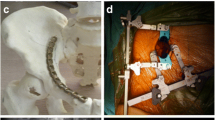

In both groups, the fracture was stabilized with a suprapectineal plate with quadrilateral buttress (PRO Pelvis and Acetabulum System, Stryker, Amsterdam, Netherlands) as the basic osteosynthesis. Bicortical 3.5 mm screws were used for fixation of the plate as it is shown in Fig. 1. For the APCS group, a 3.5 mm antegrade posterior column screw was inserted as described previously by Jung et al. outside the plate [21]. For the IAS group, a 3.5 mm infraacetabular screw was inserted as described previously by Baumann et al. through the fifth plate hole from ventral [40]. Both osteosynthesis constructs are illustrated in Fig. 1.

Fixation of a standardized generated anterior column plus posterior hemitransverse fracture with a suprapectineal plate plus an antegrade posterior column screw (A) or plus an infraacetabular screw (B). Red arrows indicate either the antegrade posterior column screw or the infraacetabular screw and the blue doted lines their respective course. The fracture lines are outlined in purple and the three main fracture lines are labeled

More precisely, it was demonstrated, that interfragmentary motion at the posterior hemitransverse fracture line (LX, shear XY) and at the high anterior column fracture line (LY) was significantly increased when an infraacetabular screw was used instead of an antegrade posterior column screw, each in combination with a suprapectineal plate. By contrast, fixation with an infraacetabular screw instead of an antegrade posterior column screw resulted in a reduced interfragmentary motion (LX, LY, LZ, shear XY) at the low anterior column fracture line. These results demonstrate that interfragmentary motion was increased at certain main fracture lines of the ACPHT fracture in both groups depending on the different screw courses. As it is illustrated in Fig. 5, the antegrade posterior column screw runs more perpendicular to the posterior hemitransverse fracture line and bridges the fracture line resulting in a higher fixation strength compared to the infraacetabular screw at this fracture line. In contrast, the infraacetabular screw runs more perpendicular to the low anterior column fracture line and bridges the fracture line resulting in a lower interfragmentary motion at this fracture line when an infraacetabular screw was used instead of an antegrade posterior column screw.